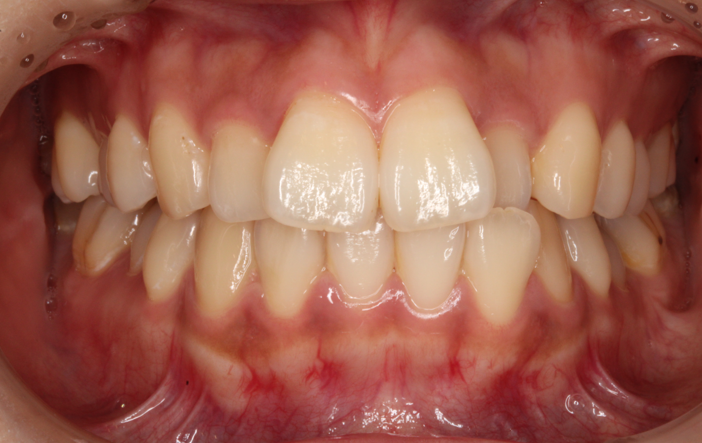

上の歯が出ている、嚙み合わせが悪い(治療期間:2年4か月/通院32回)

| 主訴 | 上の歯が出ている、嚙み合わせが悪い |

| 抜歯 | 上顎左右4 |

| 矯正の装置 | 裏側矯正(舌側矯正) |

Before